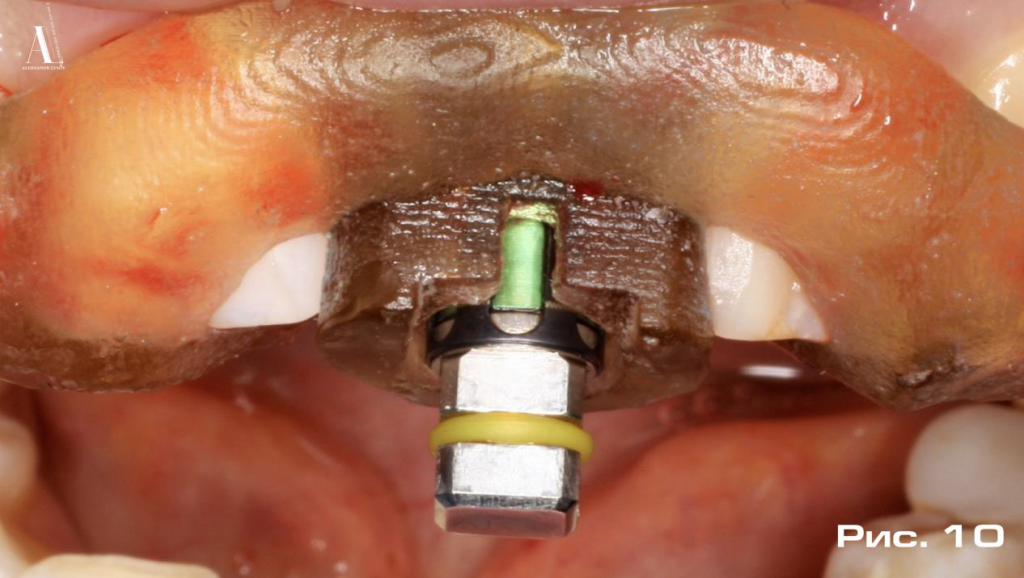

При установке имплантата использовался хирургический набор R2Kit, в состав которого входит имплантоввод со специальными метками, предназначенными для точного расположения имплантата и ориентации его антиротационного элемента в строго запланированном положении. Это достигается за счет совмещения меток имплантоввода со специальными локационными элементами направляющего шаблона (Рис. 10).